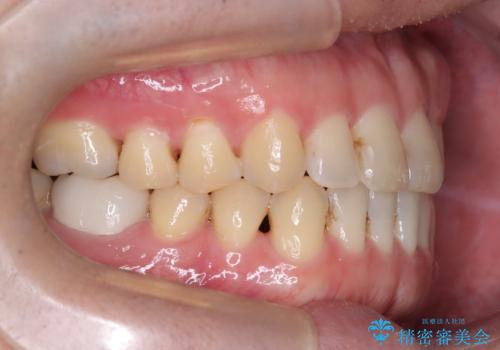

前歯が嚙んでない場合(開咬)、顎間ゴムというゴムを使用してもらうことがあります。顎間ゴムは、前歯を噛み合わせるための力を与える補助的な役割があります。

- 口腔内・歯並びの状態によっては対応できない場合があります

- マウスピース型矯正装置の長時間装着(1日20時間以上)が必須です

- 治療計画通りに進めるためには、患者様の意志が重要になります

- 矯正治療後の保定が不十分だと後戻り(元の位置に戻ろうとする動き)をします